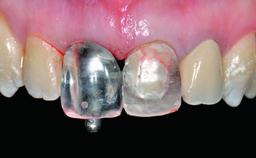

Replacement of an Ankylosed Upper Left Central Incisor: Bone Augmentation and Socket Grafting, Late Placement of an RC Bone Level Implant

Abutment Type CAD/CAM

Prosthesis Type FDP

Retention Screw-retained Screw-retained